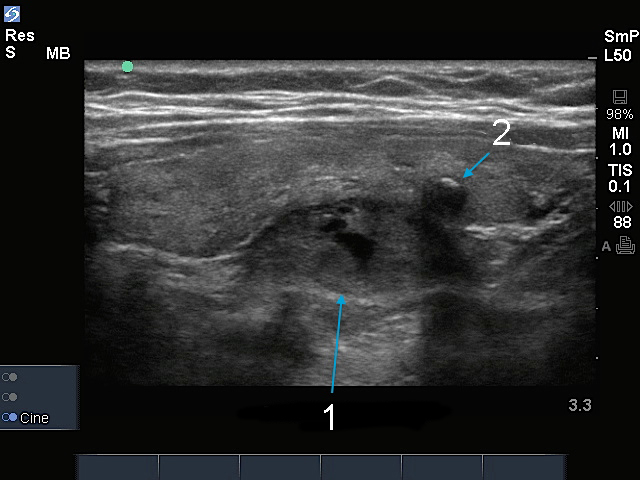

Imagen paratiroidea

Nódulo paratiroideo

Nódulo tiroideo